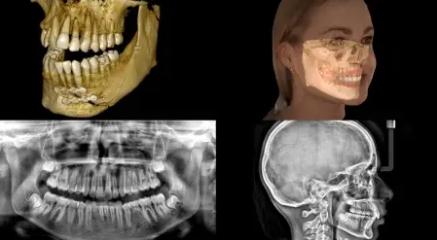

The cutting-edge CS 8200 3D panoramic and cone beam system from Carestream Dental delivers powerful versatility and precision all in one innovative package.

This next-gen model expands your field of view options for unparalleled flexibility. With nine selectable views ranging from 4x4 cm all the way up to 12x10 cm, the CS 8200 is equipped to cover virtually any diagnostic need your practice requires.

The CS 8200 3D blends 2D panoramic technology, CBCT imaging and 3D model scanning to create one powerful unit.

The CS 8200 3D offers multiple fields of view, to support all of your diagnostic needs — from routine exams to specialized ones.

This all-in-one unit is designed to seamlessly capture stunning 2D panoramic views and medium field of view 3D cone beam scans with ease. With a wide range of medium to large field of view settings from 4x4 cm up to 12x10 cm, the CS 8200 supports an impressive variety of specialized dental applications.

Whether you need detailed bitewing analysis, full jaw visualization, or targeted higher resolution imaging, this system's adaptable field of view has you covered. And as your practice grows, simply upgrade to add cephalometric capabilities for even greater clinical flexibility.